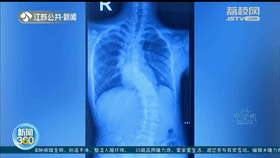

医生说,聪聪的脊柱侧弯达到87度,属于中重度畸形,12节胸椎里有5节发育异常,非常少见。手术稍有不慎,就会导致瘫痪。

8月13号,运用3D打印技术和骨科机器人导航,历经6小时“精雕细琢”,医生为聪聪重建了脊柱。